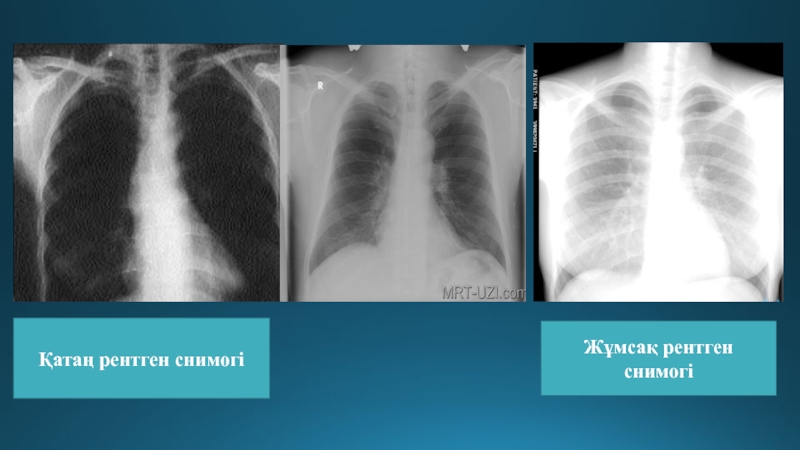

Слайд 9Қатаң рентген снимогі

Жұмсақ рентген снимогі

Қатаң рентген снимогіЖұмсақ рентген снимогі